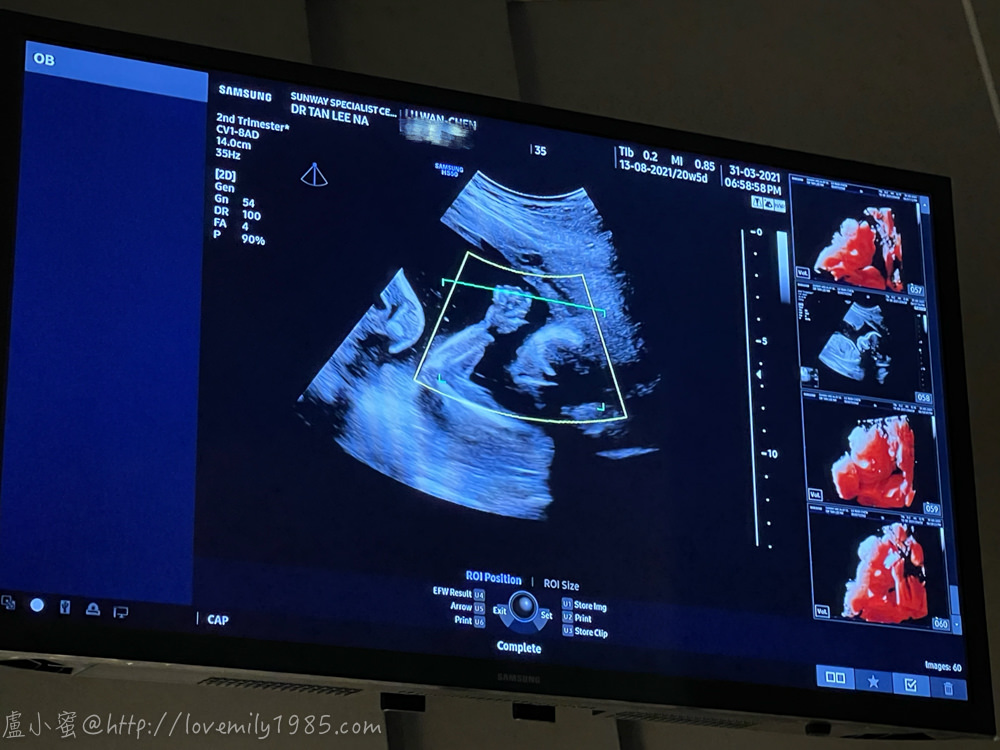

然後醫生人超好,馬上說那給他們看看寶寶的臉

他們一看說:「寶寶在笑誒!!!」

還真的誒!嘴角有微微上揚的感覺

晶大概從這時候才進入狀況吧!她前面都在飄….

這張又更明顯了一點,雖然有被手遮住

三寶會像誰呢?

好清楚的手指喔!